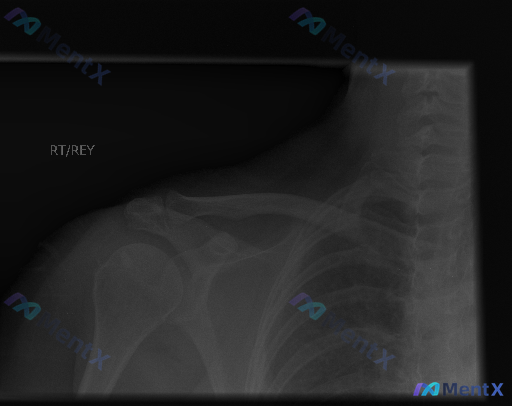

整理到一份右肩正位X光的阅片资料,先不说结论,只看影像描述的话: - 肱骨头、盂肱关节、肩锁关节对位都好,没有脱位 - 骨皮质连续,没看到透亮骨折线或骨质破坏 - 关节间隙不窄,肩峰下也没有明显钙化灶 - 软组织也没肿胀、积气或异物 但假设患者是有持续肩痛/活动受限来的,这种“影像上没发现典型异常”...